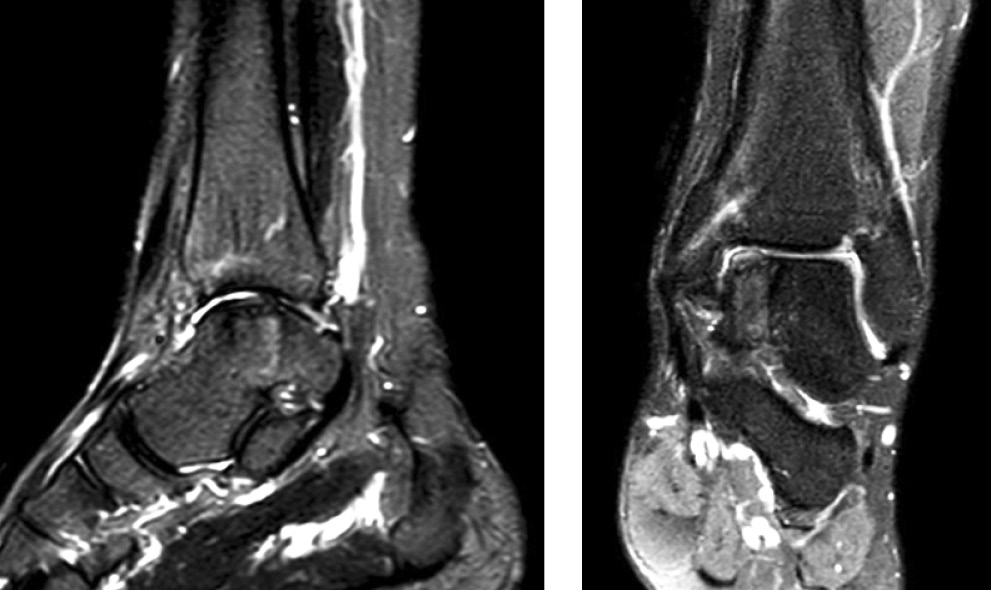

Через 12 мес. выполнено контрольное МРТ-исследование: определяются консолидация зоны остеотомии, перестройка аутотрансплантата в зоне дефекта таранной кости и формирование хрящевого покрытия (рис. 5).

Рис. 5. МРТ через 12 мес. после операции (Т2-взвешенное изображение): полная костно-хрящевая интеграция аутотрансплантата и коллагеновой мембраны

Fig. 5. MRI of the left ankle (T2-weighted image): the completed osteochondral integration of an autograft and a collagen membrane